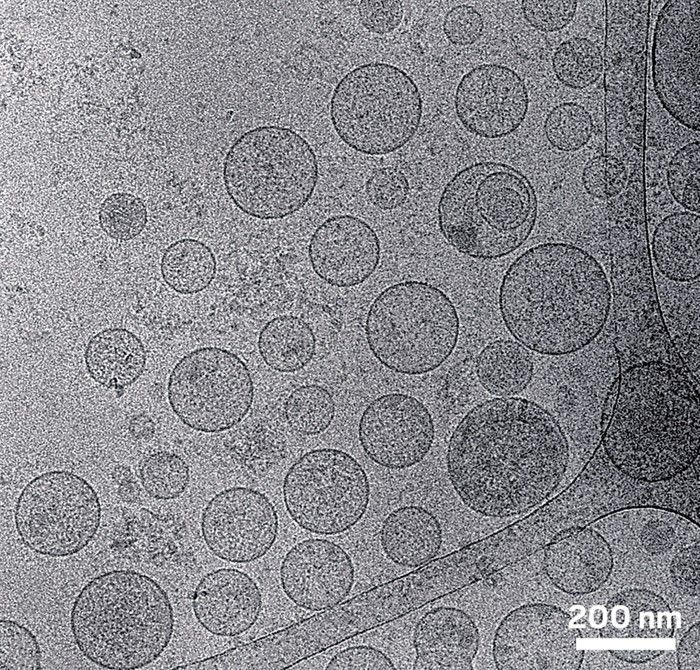

图片来源:Alain Brisson。如该电子显微照片所示,身体的大多数细胞释放各种尺寸大小的外泌体。